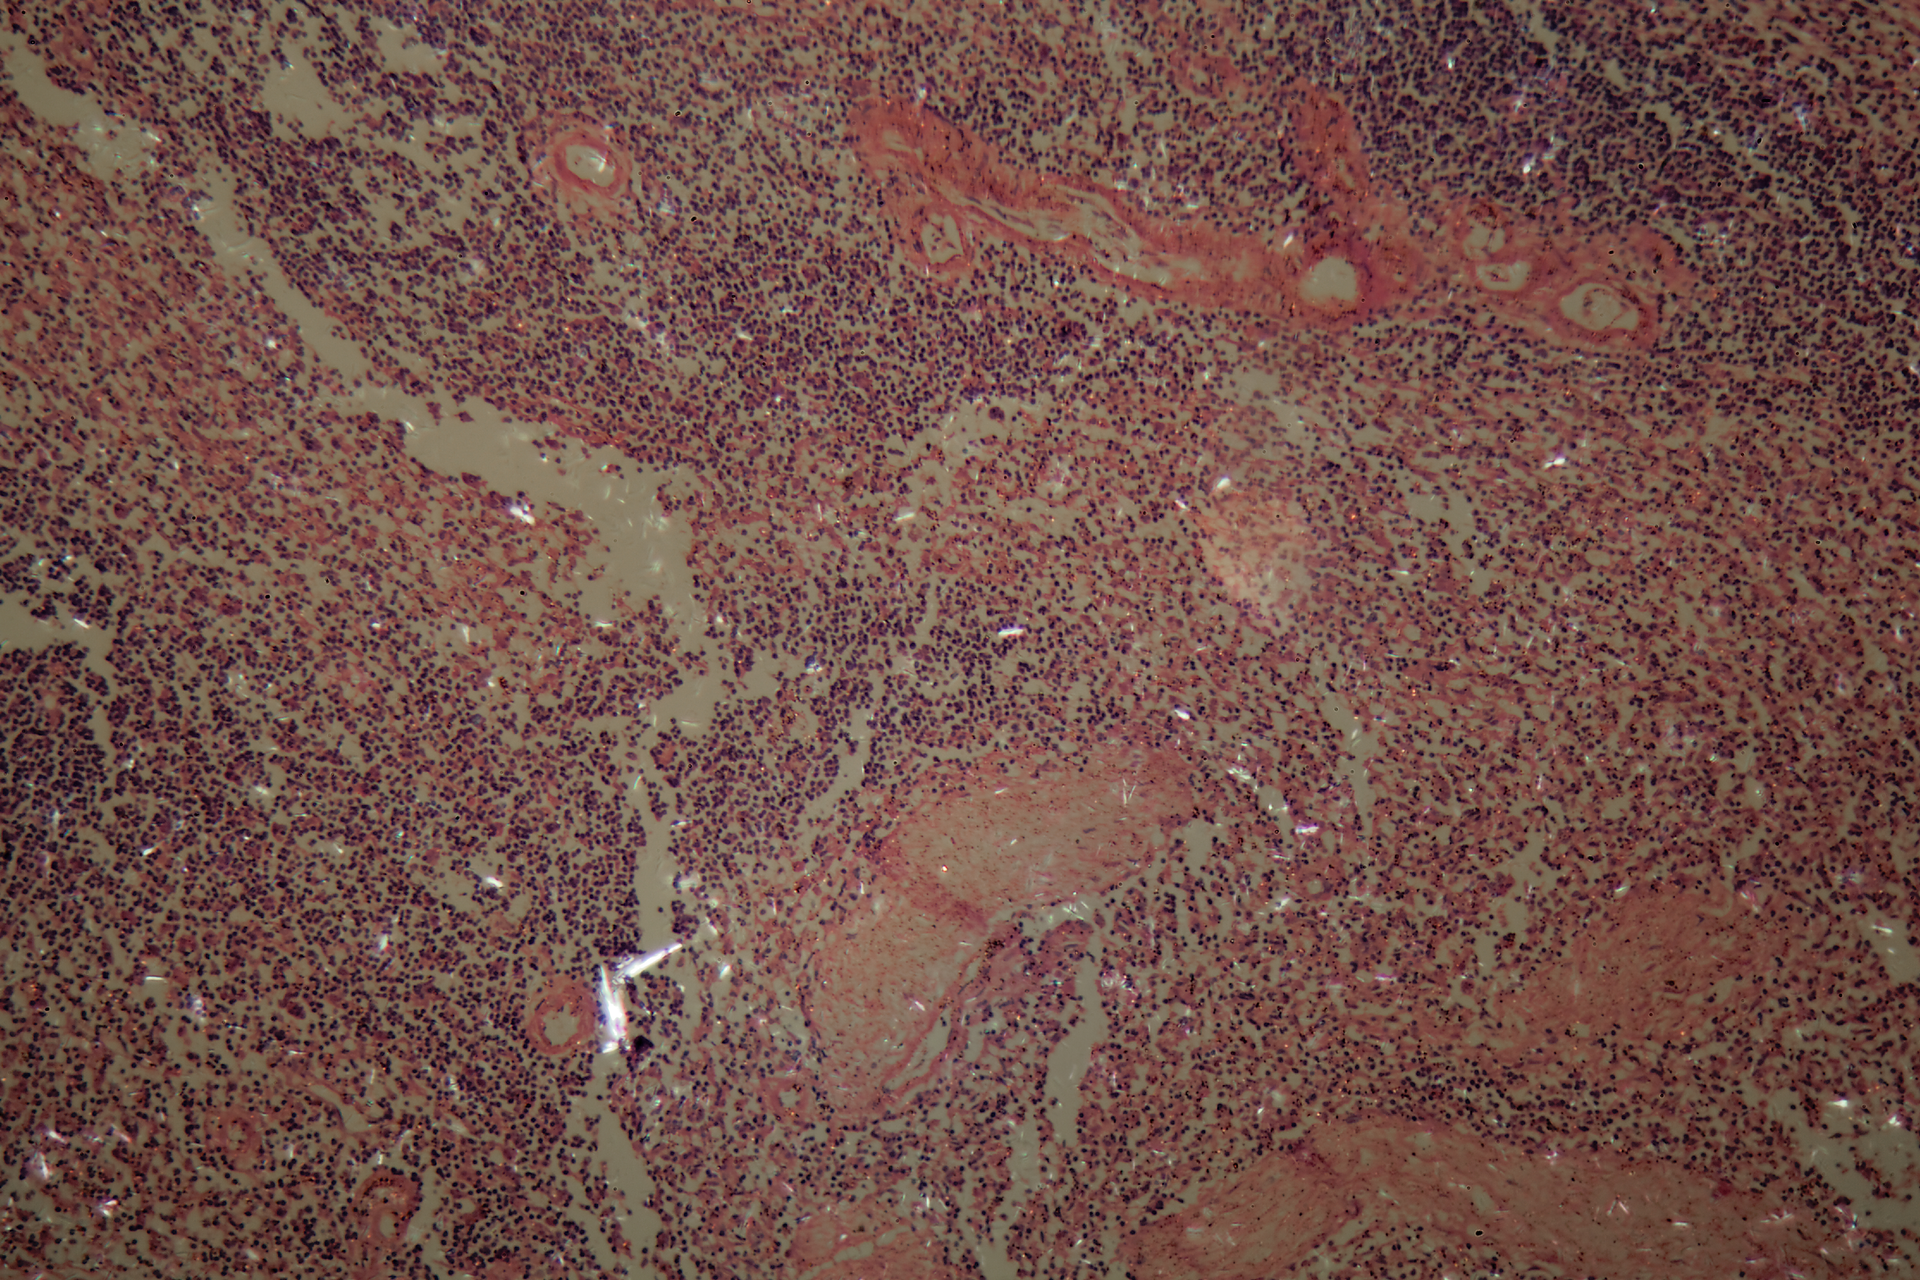

Using 3-D models of ovarian cancer tumors, scientists found differences in gene activity based on where a cell is in a tumor, demonstrating how a cell’s location and environment in a cancerous tumor can strongly influence which genes are active and the cell’s role in the cancer’s biology. More specifically, the team co-led by researchers at the National Center for Advancing Translational Sciences (NCATS), part of the National Institutes of Health, showed that gene activity in cells at or near a tumor’s surface differed from that of cells closer to the tumor center.

The approach pairs the use of a technology to reveal the genetic activity of single cells within a tumor with fluorescent dyes that spread into tumors. The work could allow researchers to study how the same diseases can vary in people and progress differently. This research could help clinicians identify treatment strategies focused on specific areas in tumors, which could lead to better therapies for cancers and other diseases. The team reported its results June 21 in Cell Systems.